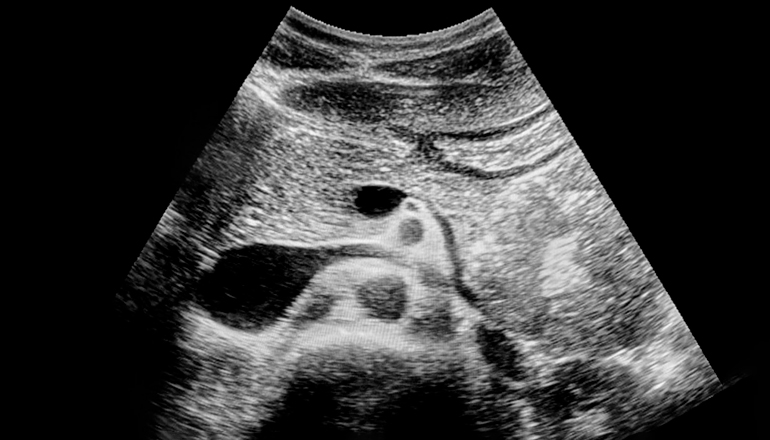

Ультразвуковое исследование (УЗИ) поджелудочной железы — один из наиболее информативных и доступных методов инструментальной диагностики. Для получения корректных результатов исследование требует от пациента грамотной подготовки. Без нее даже самое современное оборудование не гарантирует достоверных результатов.

Поджелудочная железа расположена глубоко в брюшной полости, рядом с кишечником. Такое соседство затрудняет ее визуализацию. Все дело в кишечных газах и остатках пищи, которые создают помехи. Поэтому УЗИ поджелудочной считается одним из самых требовательных с точки зрения подготовки.